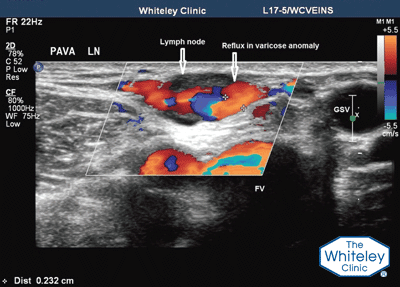

We diagnose PAVA as small, refluxing vessels in legs with primary varicose veins and no history of surgery, trauma, or infection in the area that show one or more of three patterns of distribution: lymph node pattern – PAVA arising directly from groin lymph nodes; peritruncal pattern – PAVA wrapping around the great, small, or anterior accessory saphenous veins; and atypical pattern. PAVA are predominantly found within the saphenous fascia, but components have been found to emerge into the superficial and deep venous compartments.

Duplex ultrasound showing PAVA (primary avalvular varicose anomalies) – red and blue colours show blood flow in the veins. PAVA first described in 2014 by the The Whiteley Clinic